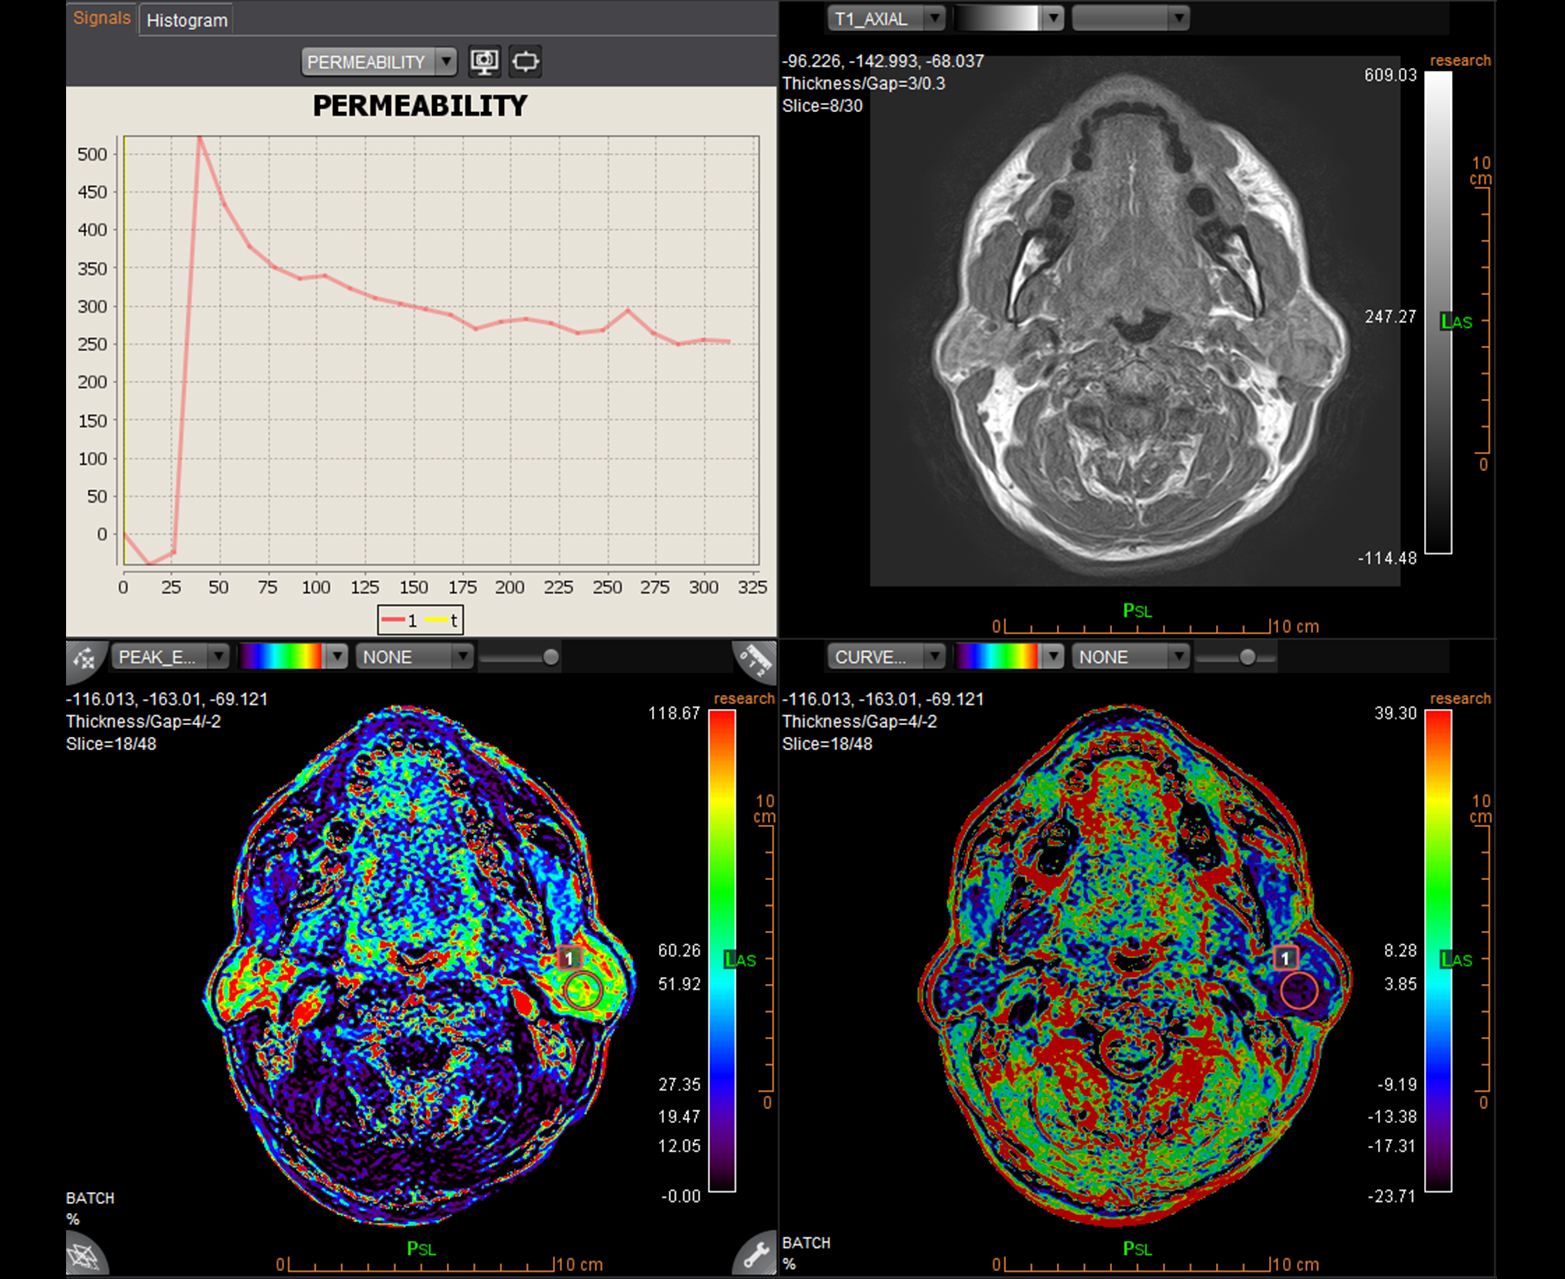

Автоматически и точно рассчитывает качественные и количественные карты проницаемости.

Количественные карты проницаемости головы и шеи